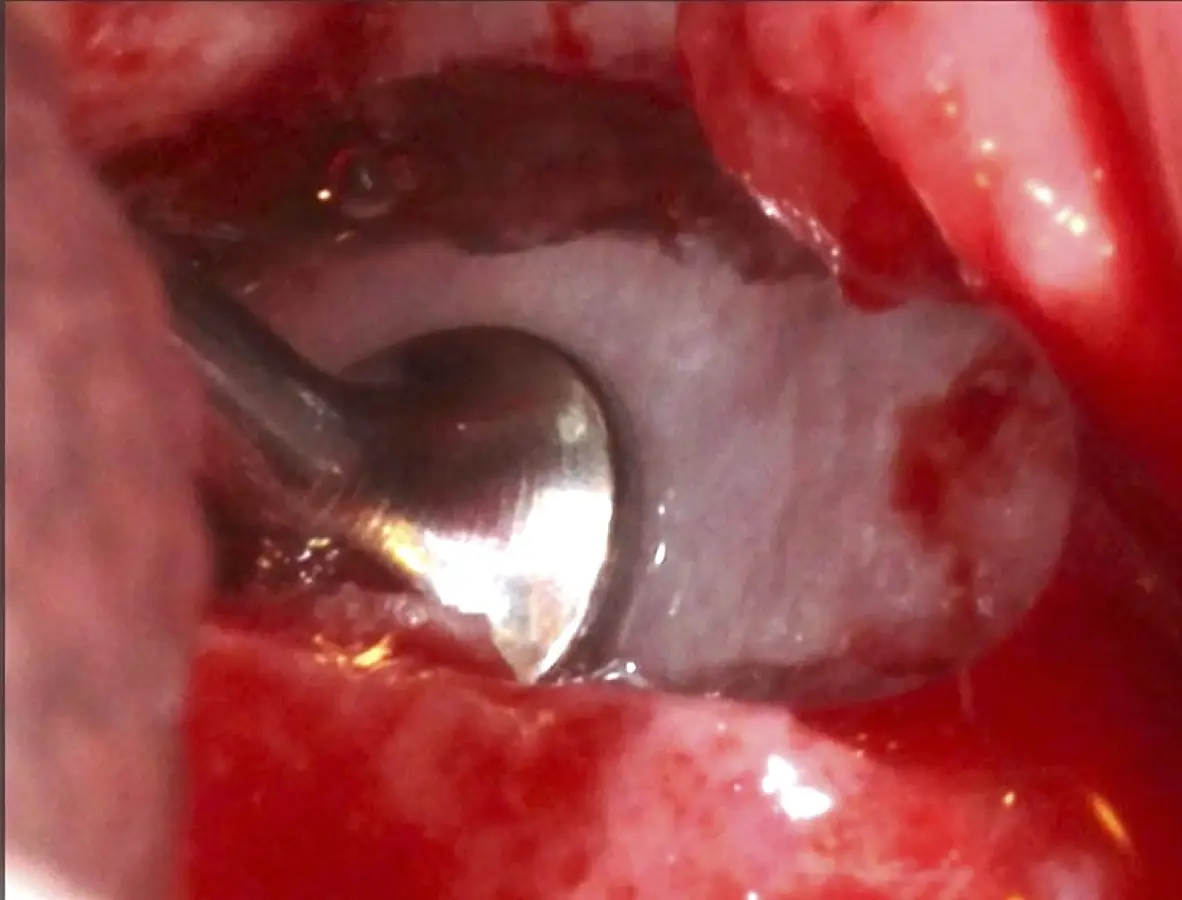

Figura 24. Fractura del bloque óseo con la ayuda de un martillo e instrumento romo.

Figura 25. Introducción del bloque óseo de la pared lateral dentro del seno maxilar: inicio del desprendimiento de la membrana con el inserto de presión hidráulica.

Figura 26. Decolado de la membrana de Schneider hasta la pared medial del seno maxilar (a). Desplazamiento de la pared ósea lateral al interior del seno maxilar transformándose en parte del techo de la ventana o nuevo piso del seno (b).